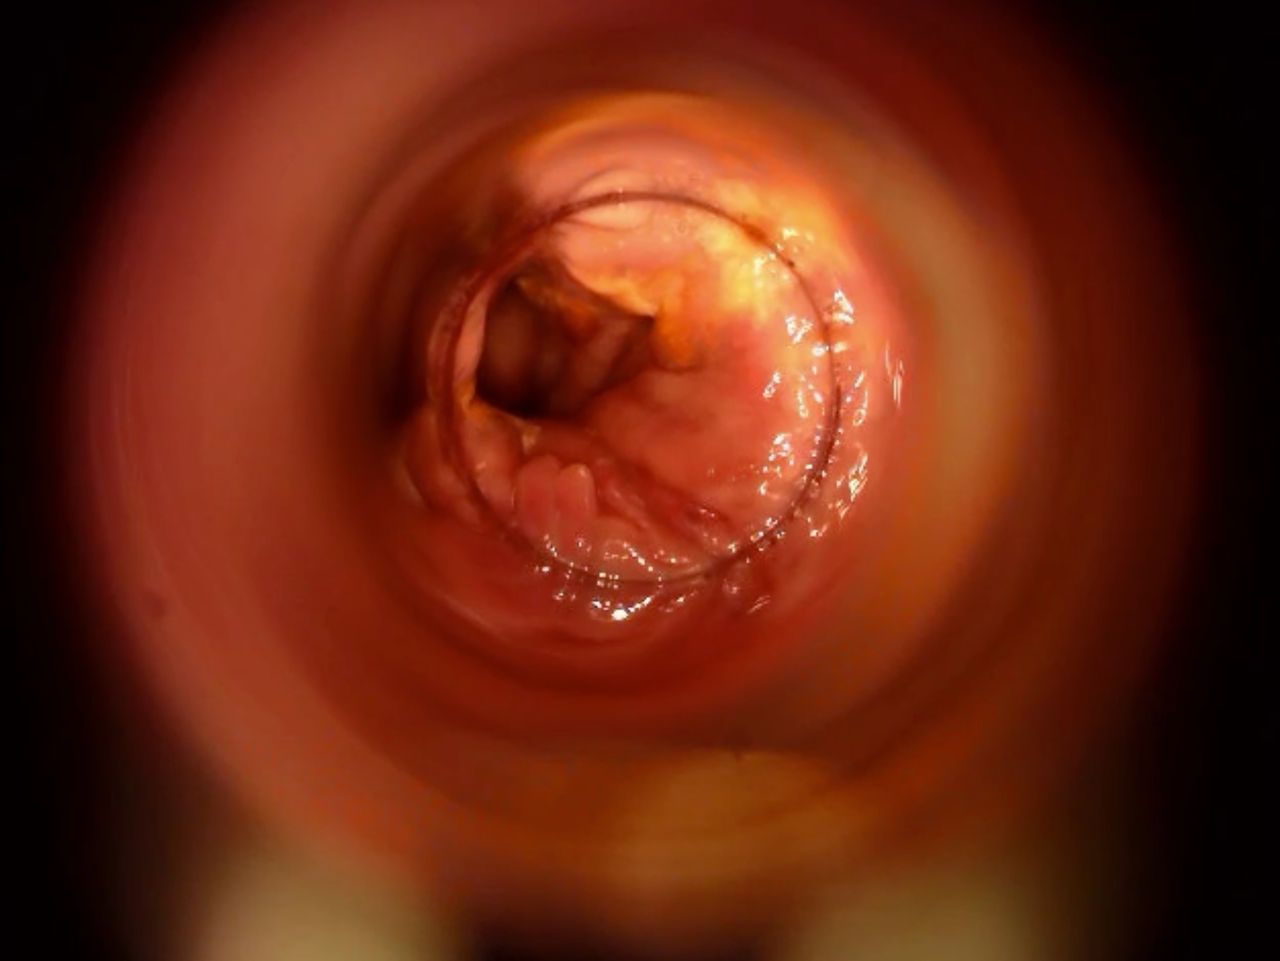

La cura delle emorroidi patologiche, finalmente senza dolore

Come Chirurgo Vascolare, sono perfezionata in Proctologia da molti anni, e molti altri ne ho passati direttamente in sala operatoria, praticando l'emorroidectomia con metodo Milligan-Morgan.

Durante la mia esperienza come Chirurgo Protcologo, ho visto personalmente come i trattamenti chirurgici disponibili, benché necessari, fossero comunque abbastanza invasivi per il paziente, specialmente nel decorso post operatorio.

Fortunatamente, negli ultimi anni sono stati messi a punto protocolli non chirurgici molto avanzati, che ho personalmente studiato ed approfondito con molto interesse.

Tra questi, ho cominciato ad utilizzare il trattamento sclerotizzante con scleromousse stabilizzata ad aria sterilizzata, che considero ormai il 'Gold Standard' per il trattamento non invasivo e permanente delle emorroidi patologiche.

Ho quindi attrezzato il mio studio con il moderno Videoproctoscopio Digitale, nonché con avanzate pompe miscelatrici ad aria sterilizzata, in grado di ottenere una scleromousse stabilizzata di grande qualità, perfetta per il trattamento emorroidale.

Grazie a questo protocollo, posso risolvere casi anche molto gravi di prolasso emorroidale, garantendo una risoluzione definitiva in oltre il 95% dei casi clinici.

Il tutto, senza il minimo dolore o disagio per il paziente.